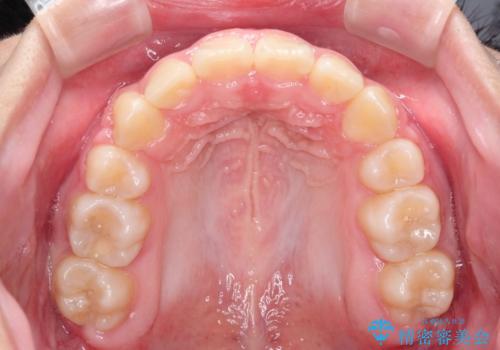

抜歯矯正で口元に変化を ラビアル・ワイヤー矯正でEライン

- 上下左右4本の小臼歯を抜歯、ラビアル・ワイヤー矯正を計画した。

抜歯をして第1小臼歯分のスペースを獲得することにより、ガタつきの改善と前歯のリトラクトをおこない、横顔の印象もすっきりとし、整ったEラインを作ることができました。